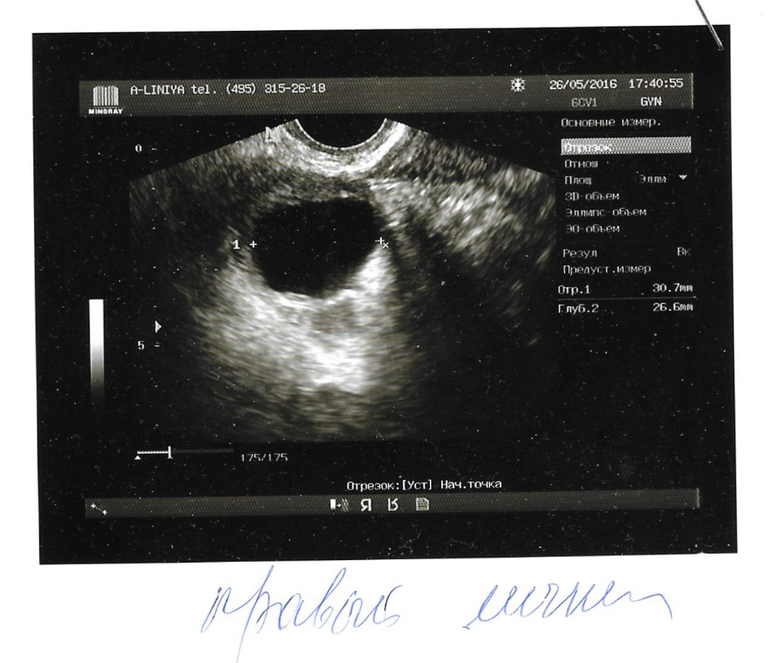

Узи может быть ошибочным

Узи может быть ошибочным 113 фотографий